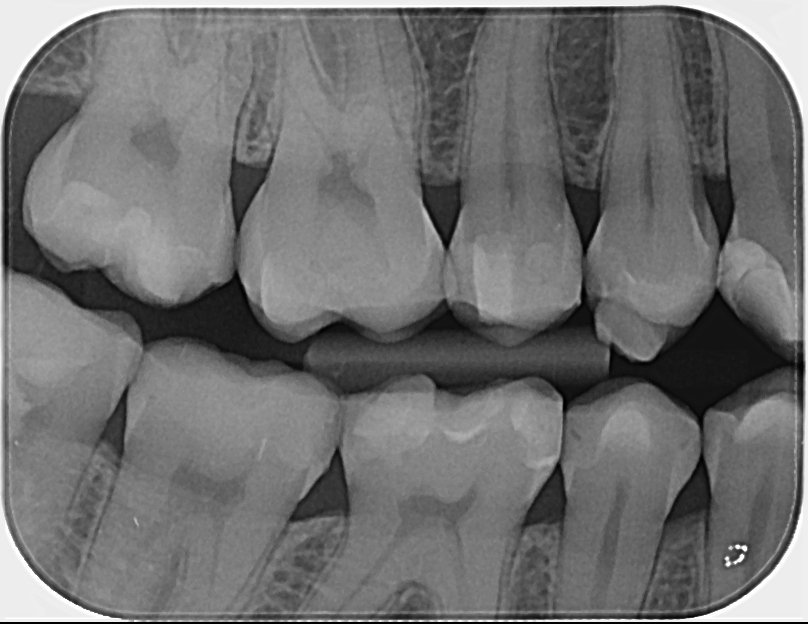

Здравейте, може ли мнение за тази снимка. Според зъболекаря, при когото бях при прегледа не се вижда нищо. А имам ужасна мигрена и имам чувството, че горе 7ми зъб ме боли.

Мисля, че 5+ години. А от снимката виждат ли се проблеми или трябват още снимки или друг метод за диагностка?

Под този ъгъл сниман зъбът не се виждат проблеми.

Аз бих проверила за чуватиелнсот/оголване в шиечнага зона (на снимката няма как да се види).

Как зъбът реагира на термични дразнения (топло/студено).

Реакция при почукване на зъба.

Реакция при стискане на зъба.

Ако всичко е отрицателно бих го изключила като евентуален източник на болка.

Вашият стоматолог направил ли е някакви допълнителни изследвания (като някое от тези, които съм изброила)?

Благодаря ви много за изчерпателния отговор. Правиха почукване и тест с нещо като лед и имах само чувствителност от студено на този и няколко други зъба, но това преди месец и нещо. Вероятно ще сменя пломбата за да ми е спокойно.

На снимката изглежда, че пломбата Ви е добре направена и не се вижда да има вторичен кариес, т.е. не би следвало болката да е от зъба, особено щом не сте реагирали и от студено и шиечната зона е добре. Сменяйки пломбата с друга, няма да постигнете нищо, най-много зъбът да се травмира и да започне да се самоумъртвява. Не изглежда проблемът да е от зъбен произход.